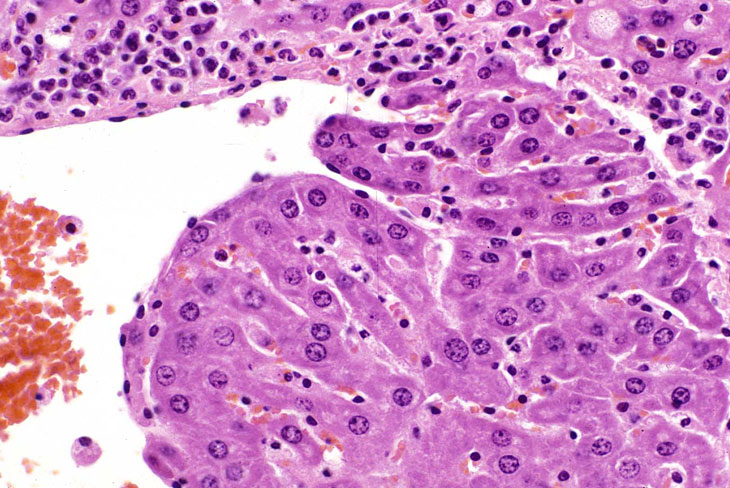

In some foci of cellular alteration, primarily basophilic foci, hepatocytes may occasional be seen to protrude into the lumen of hepatic veins. They are usually lined by a layer of flattened endothelial cells. This change has been considered by some to represent a form of microinvasion and such lesions have been diagnosed as hepatocellular carcinomas, possibly motivated by the fact that most are seen within foci induced by treatment with hepatocarcinogens. However, similar changes are occasionally seen in untreated mice and may not necessarily be associated with a focus of cellular alteration. Consequently, we cannot be certain that this change is actually a microcarcinoma. Two clusters of hepatocytes protruding into a large hepatic vein.

Another example of protrusion of hepatocytes into an hepatic vein.